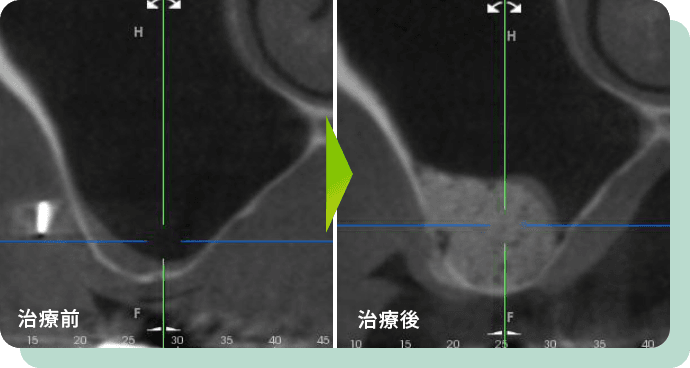

インプラント治療に必要な骨が足りない場合は、GBR、ソケットリフト、サイナスリフトといった手法を用います。

GBRとは、Guided Bone Regeneration(骨誘導再生術)のことを指し、人工の骨などを用いて、不足している骨を造成していくことを言います。

インプラント治療を希望される患者様の中には、骨がやせ細ってしまっている患者様などもいらっしゃいます。

実際に、骨がやせ細ってしまっている場合は、インプラントが骨の中に収まらずにはみ出してしまうこともあり、そのまま被せものをおこなった場合には、歯ぐきから露出した状態になってしまいます。

そういった事を防ぐために、必要な箇所に骨を造成することがあり、その方法をGBRと言います。

上顎臼歯部の上方には上顎洞という空洞があり、インプラント治療をするにあたり、骨の量(たかさ)が不足していることがあります。

そのような場合、以下のような手法を使って対応することが可能です。

上顎(上あご)の骨が不足している場合にインプラント埋入と同時に自身の骨・人工骨などの移植を行い、足りない骨を補う手法です。

ある程度既存の骨が残っていることが条件となります。